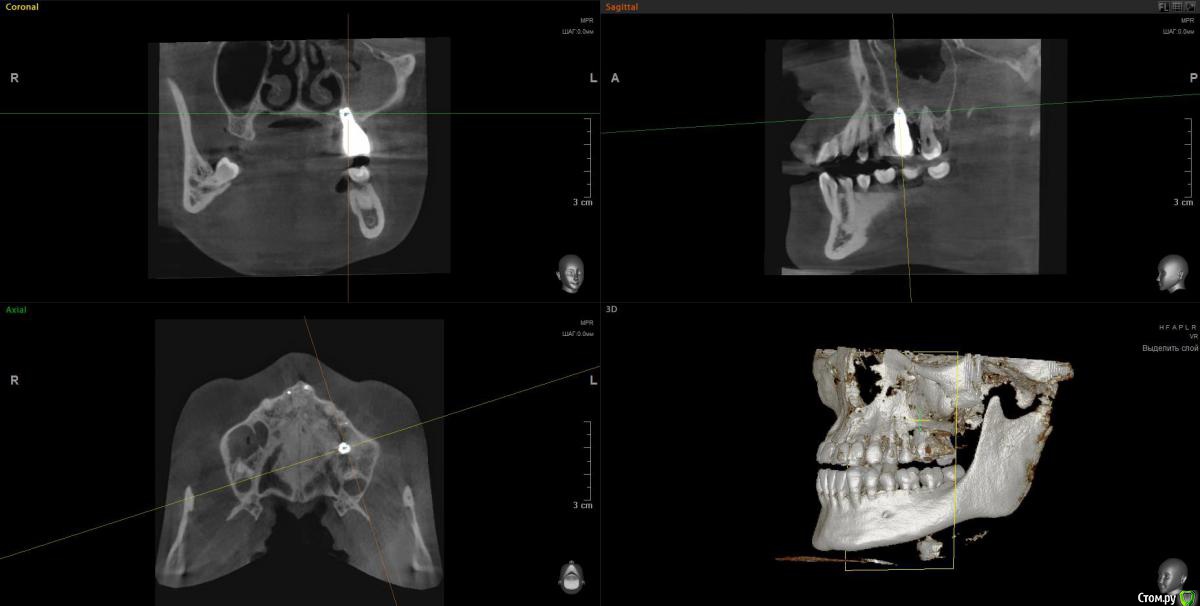

wladdX Опубликовано 9 апреля, 2020 Поделиться Опубликовано 9 апреля, 2020 Несколько скринов Ссылка на комментарий

Lunar Опубликовано 9 апреля, 2020 Автор Поделиться Опубликовано 9 апреля, 2020 Несколько скринов25_1.jpg25_2.jpgimp_1.jpgimp_2.jpg27_1.jpg27_2.jpgспасибо за скрины Ссылка на комментарий

Irouil Опубликовано 9 апреля, 2020 Поделиться Опубликовано 9 апреля, 2020 https://yadi.sk/d/FRKX9i80axqaUgПосмотрел я Ваше КТ. На мой взгляд, проблема чисто ЛОРовская, но... ЛОР врач может придраться к состоянию в полости рта и формально будет прав, поэтому Сначала проверить на витальность 7ку (вероятнее всего все же придётся депульпировать) Клинически осмотреть 5-ку (стоматологу терапевту). Потом к лору. Имплантат к пазухе вообще не имеет никакого отношения 1 Ссылка на комментарий

Irouil Опубликовано 10 апреля, 2020 Поделиться Опубликовано 10 апреля, 2020 На мой взгляд удалять имплантат пока не надо, но нужна очная консультация пародонтолога и новая коронка на имплантате Ссылка на комментарий